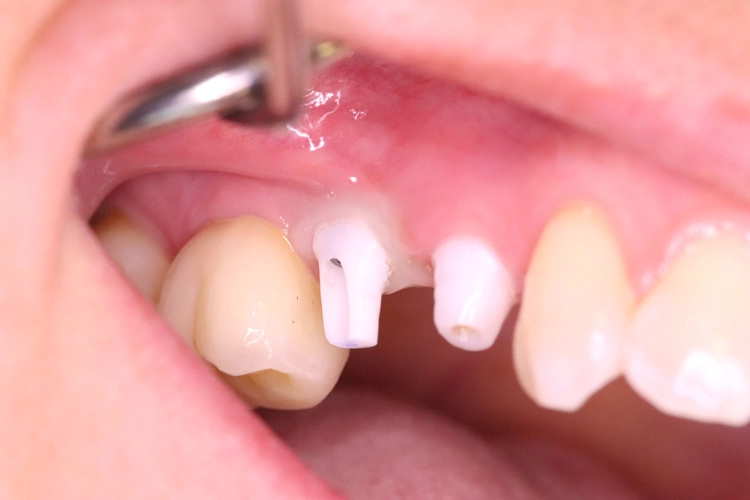

Nach der ersten klinischen Befundaufnahme und Fotodokumentation der Ausgangssituation (Abb. 1) wurde zur Ergänzung des klinischen Befundes eine Einzelzahnaufnahme erstellt (Abb. 2). Vom Oberkiefer wurde eine Abformung genommen, um eine Tiefziehschiene herzustellen. Diese wird direkt am OP-Tag genutzt, um eine provisorische Krone herzustellen.

Aufgrund der traumatischen Extraktion des ankylosierten Zahnes, die zu einer Osteotomie wurde (Abb. 3), fehlten die vestibuläre und palatinale Lamelle (Röntgenkontrollbild während der Osteotomie, Wurzelrest noch vorhanden Abb. 4). Dieser Wurzelrest wurde entfernt. Bei dem geringen Restknochenvolumen war eine Sofortimplantation nicht mehr indiziert.